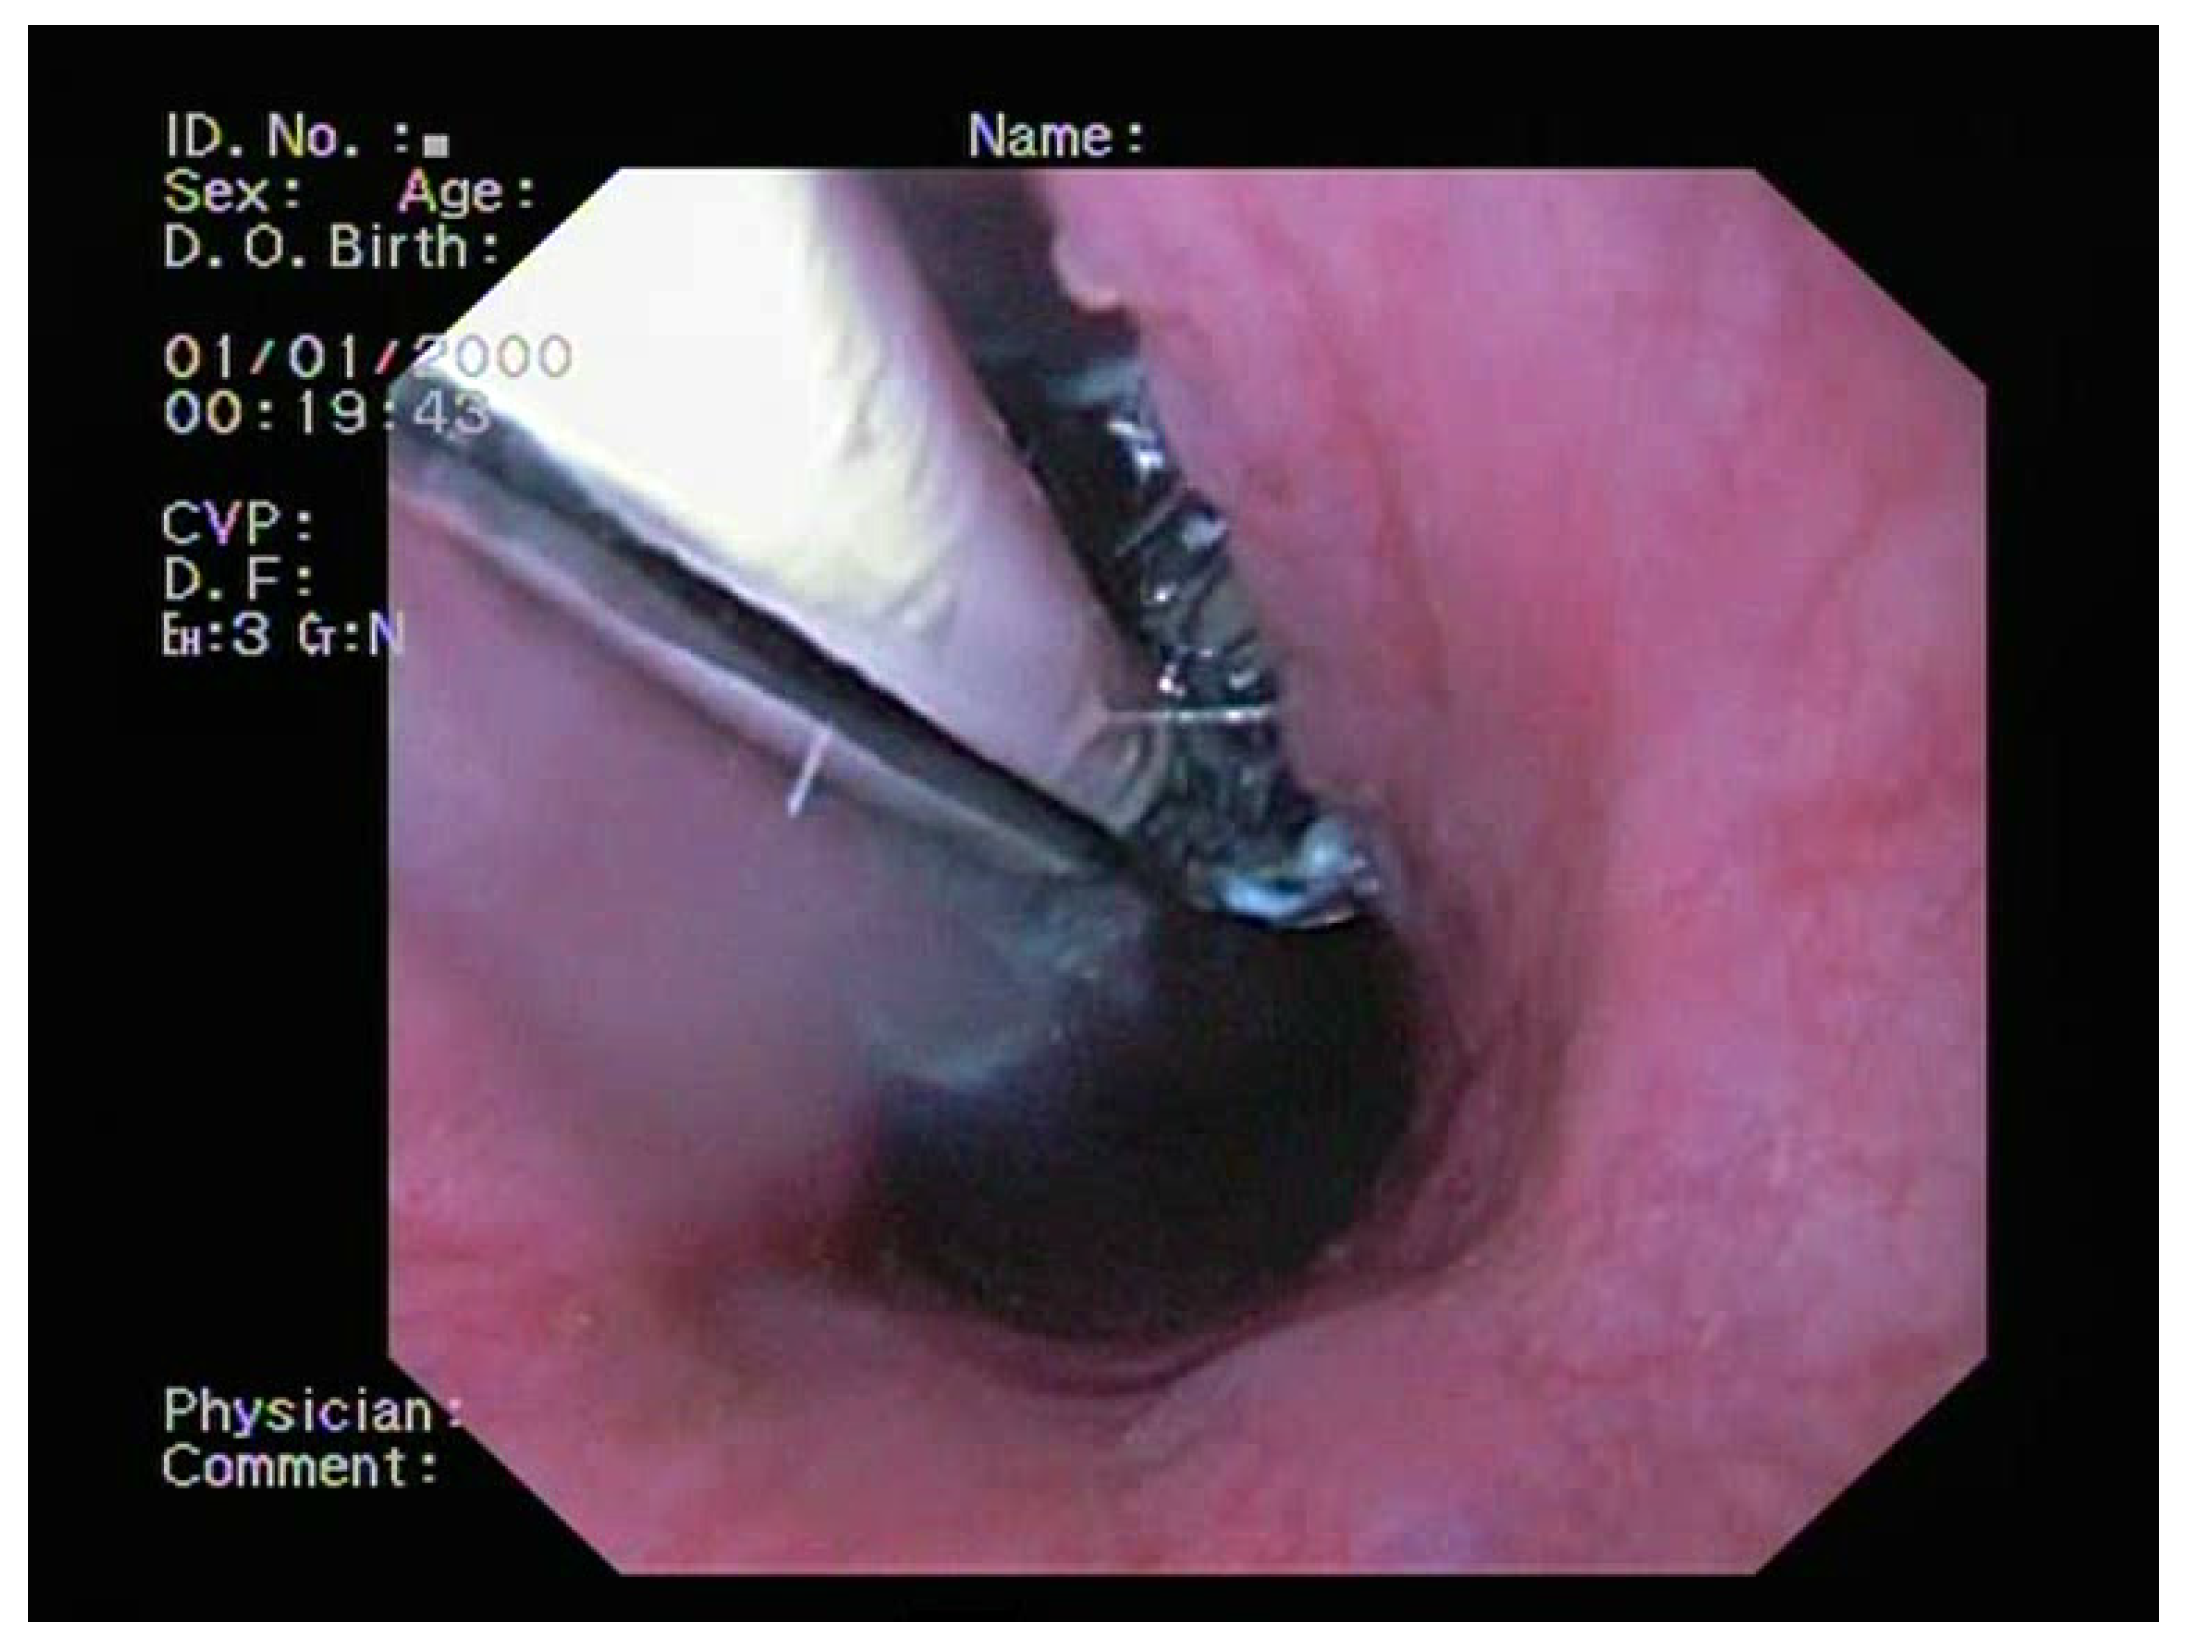

2.2. Bronchoscopy